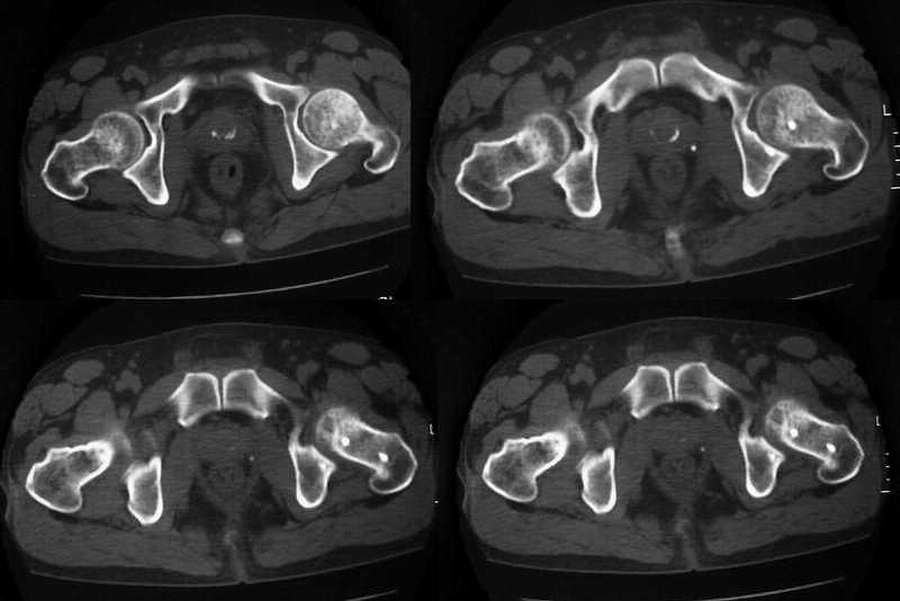

标题: CT2677:[原创]男54岁,左髋疼痛三月 [打印本页]

标题: CT2677:[原创]男54岁,左髋疼痛三月

盆腔静脉石;前列腺钙化;左股骨骨岛。

左侧股骨头无菌性坏死,盆腔静脉石;前列腺钙化;左股骨骨岛。

双侧都需要考虑股骨头无菌性坏死,其中左侧最为明显(囊变和碎裂)

本例就此图像无法明确有无股骨头缺血性坏死。

以股骨头缺血性坏死部位分为股骨头顶部和中心部持重区坏死与及其周边非持重区坏死。而本例左侧明显囊变在头颈结合部的下方。若两边都有问题,那么骨盆也显示密度不均,有问题吗?建议查mr或ect。

缺血性坏死的ct表现:(1)早期主要表现为正常股骨头骨小梁星状征变形,表现在从股骨头中央到皮质下有点状或小道样致密的骨增生,周围呈丛状或相互融合,关节下非持重部多以骨质疏松为主,股骨头完整,无明显碎裂;(2)病变区出现小范围坏死及小囊状影,继之股骨头坏死以持重区为明显,中央多呈楔形或周围新月状的骨密度增高坏死,囊变边缘硬化,正常骨结构可完全消失,坏死周围骨质梳松;(3)股骨头软骨头下骨折、塌陷,关节面不规则,关节间隙宽窄不一,股骨头可有轻中度变形,可有碎骨片落入关节腔;(4)晚期股骨头变扁、碎裂增加,外形不规整,呈“蕈伞”状畸形,其内见骨质增生硬化及透光区混合密度影,关节间隙变窄,髋关节退行性变。

双侧股骨头坏死可能性大,左侧为著,建议mri。

双侧股骨头无菌坏死,左侧为著